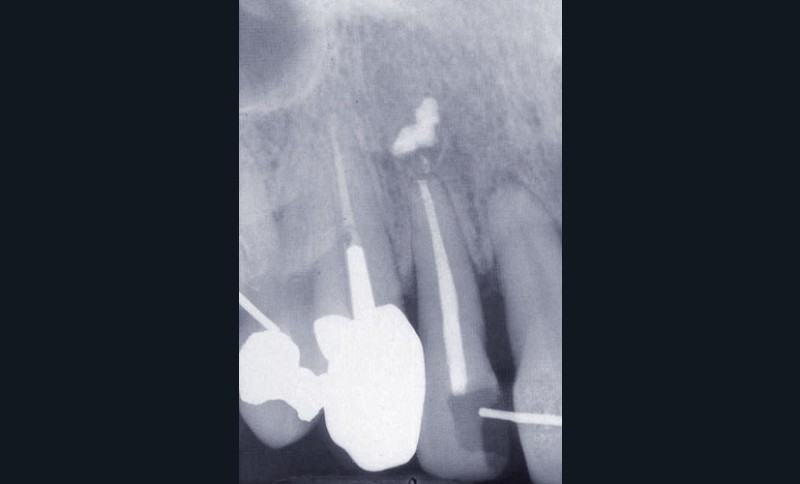

Les examens cliniques et radiographiques montrent une parodontite chronique généralisée (fig. 1a à m).

Nous décidons d’entreprendre une thérapeutique initiale parodontale classique dans tous les secteurs, y compris l’extraction de 24, un bridge de 45 à 48 avec 46 en pontique, un bridge complet de contention de 17 à 27 sur 11 piliers dentaires et une greffe épithélio-conjonctive sur 31. Cette dernière ne sera jamais réalisée. Le bridge maxillaire permettra de réduire le surplomb antérieur et d’améliorer le sourire de la patiente, ce qui constitue l’une de ses demandes.